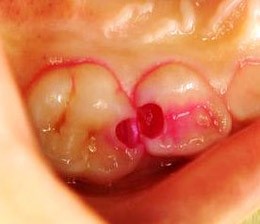

露出した神経を守る「直接覆髄法」

「直接覆髄法(ちょくせつふくずいほう)」は、虫歯の治療中に神経が一部見えたときに行う方法です。

露出した神経の部分に直接薬を塗って保護し、その上に詰め物をします。

神経の露出が小さく、炎症が軽い場合に適しており、神経を残す可能性を高められる治療です。